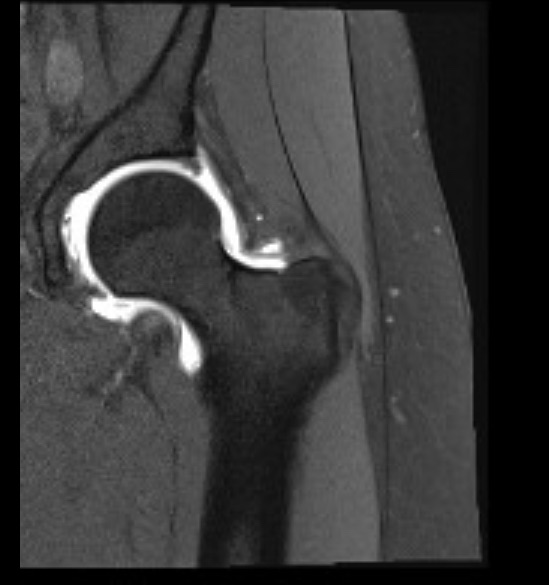

At my 3-month post-op appointment, my surgeon lifted all my restrictions and said I can return to all activity, “just listen to [my] body.” She measured my X-rays (above) and said my lumbar curve decreased 20 degrees, and the thoracic is the same. Also, I grew half an inch. I showed her the scoliosis program I found in New Hampshire, and she was all for it. I’ve booked a furnished apartment in New Hampshire 4/20-5/31 and scheduled the 12 sessions of treatment at the PT clinic there. I’m hopeful that will help with my back pain, and maybe even reduce my thoracic curve. And right before that, I’ll be attending Bionicon!

I’m walking without the cane and my balance feels back to how it was pre-surgery. My hip pain is still gone, but my low-back pain is where it was pre-surgery. The pain in my ribs is still intense. I wake up with my pain at a 4-5 and by the end of the day it’s an 8-9. The pain matches the compression you can see from these pics (morning on the left, bedtime on the right).